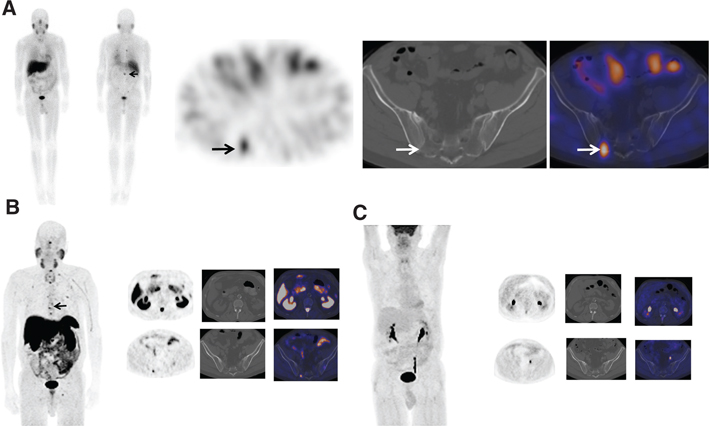

Fig 9

Figure 9 A 55-year-old woman with metastatic paraganglioma having an initial Ki67 proliferation index of 25% and strong SSTR2A immunostain but without SDHB mutation on germline testing. (A) Ga-68 DOTATATE PET/CT maximum intensity projection (MIP) images of the skull vertex to the proximal thigh on the left show widespread somatostatin receptor-positive metastatic disease, with progressive disease on the right image with enlarging pelvic osseous lesions (arrows). (B) Ga-68 DOTATATE PET/CT axial fused PET/CT, axial PET, and sagittal fused PET/CT images show enlarging vertebral lesion (arrows) on the current study (top images) as compared to the prior (bottom images).